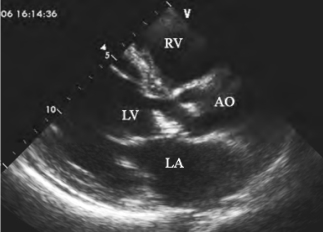

图13-19 主动脉瓣赘生物二维超声图

左室长轴示附着于主动脉无冠瓣的絮状团块回声,边缘毛糙,舒张期脱入左室流出道,为感染性心内膜炎赘生物